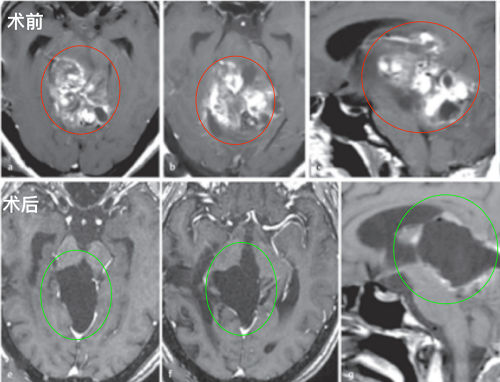

图:术前MR检查,轴位、矢状位MR显示较大脑干肿瘤占位,信号不一,从中脑两侧延伸压迫到丘脑、脑桥和小脑。

术后影像复查:轴位(e,f)和矢状位(g)T1加权增强MRI检查显示,外生型毛细胞星形细胞瘤被成功切除。病人没有出现手术相关的神经功能损伤,随后的随访病程平安无事。

图:术前术后脑磁共振对比,较大脑干胶质瘤全切,无神经脑组织损伤。